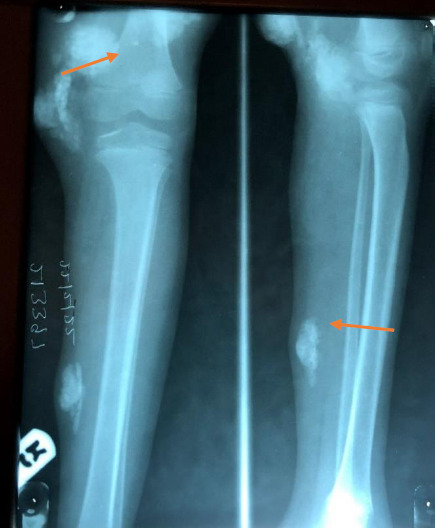

Case presentation: We present this index case of a 6-year-old child who was brought to the clinic by her parents on account of multiple subcutaneous swelling of two years' duration on her lower limbs before she presented at our outpatient clinic. The swellings started from the knee joints and were associated with difficulty in walking. A provisional diagnosis of multiple soft tissue swelling was made before some of the swellings were excised. An excisional biopsy of some of the masses on the lower extremities was done, and histological examination revealed gouty tophus. She was then placed on oral febuxostat. Her clinical condition has improved significantly; she is on continuous follow-up at our facility's paediatric orthopaedic outpatient clinic. Hitherto, gouty tophus has been recorded in juveniles and young adults, but it may present in any child below the age of five years.